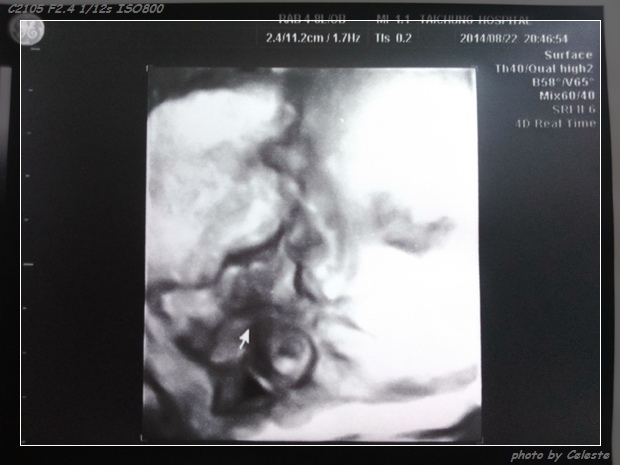

*攝於W30。現在空間變小,已經無法拍攝到這麼清楚的畫面了。就等北鼻出來跟我們見面囉!